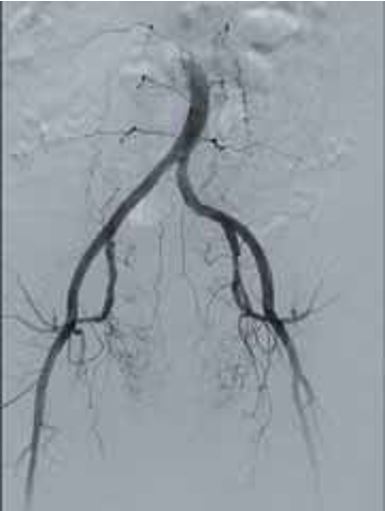

· Режим дослідження кінцівок (Dynamic Trace) передбачає рух деки столу за напрямком поширення контрастної речовини по периферичних судинах в режимі рентгенографії;